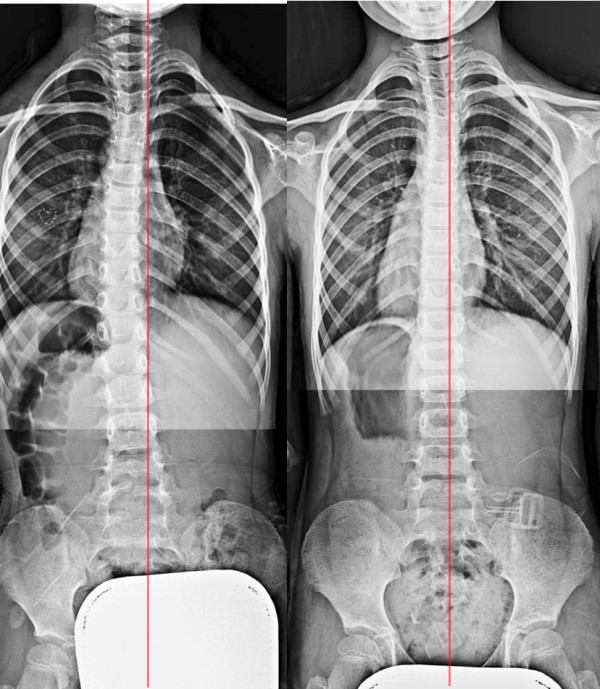

증상 : 몸이 휘었다. 학교 척추측만증 검사

치료기간(횟수) : 45회 치료, 6개월